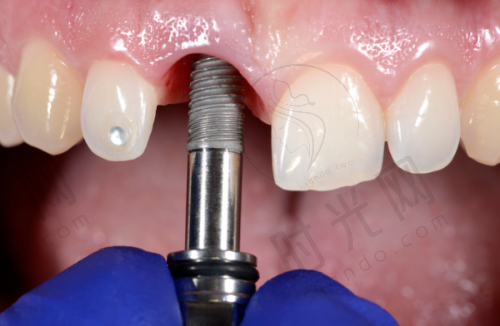

- 螺丝松了:重新拧紧或换螺丝

如果只是上面的牙冠螺丝松了,医生会用特殊扳手拧紧,就像拧自行车螺丝一样简单。要是螺丝滑丝了,换个新螺丝就行,全程微痛,当天就能用。